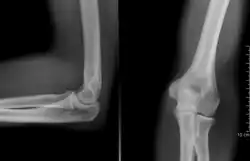

Nos ossos, a radiografia acusa fraturas, tumores, distúrbios de crescimento e postura. Nos pulmões, pode proporcionar o diagnóstico da pneumonia ao câncer. Em casos de ferimento com armas de fogo, ela é capaz de localizar onde foi parar o projétil dentro do corpo. Para os dentistas, é um recurso fundamental para apontar as cáries. Na densitometria óssea, os raios X detectam a falta de mineral nos ossos e podem acusar a osteoporose, comum em mulheres após a menopausa. Na radiografia contrastada, é possível diferenciar tecidos com características bem similares, tais como os músculos e os vasos sangüíneos, através do uso de substâncias de elevado número atômico (iodo ou o suspensão de sulfato de bário). Ainda, o raio-X possibilitou o surgimento de exames como a tomografia axial computorizada (TAC) que, com ajuda do computador, é capaz de fornecer imagens em vários planos, de forma rápida e precisa, utilizando quantidades mínimas de radiação.

Röntgen realizou variados testes com diferentes objetos posicionados entre os raios e a placa. Enquanto segurava esses objetos para realização dos testes, pode visualizar um leve esboço dos ossos de sua mão. Aprofundando os testes, Röntgen trocou a placa por uma chapa fotográfica e, a partir disso, teve certeza de que havia descoberto algo interessante.[2]

Temos a radiografia da mão da esposa de Röntgen, como sendo a primeira radiografia realizada.